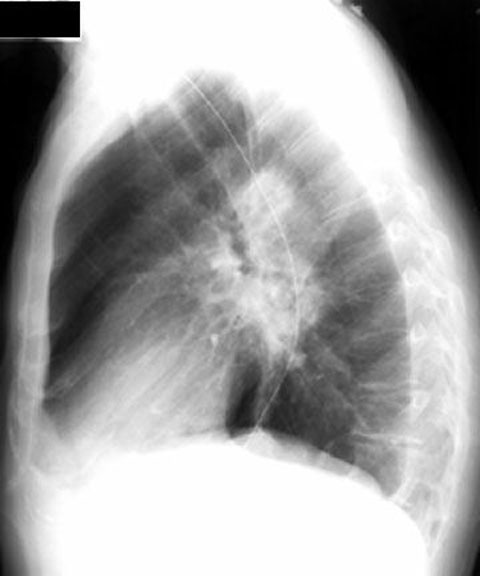

Case 4

Lateral

Labeled Image

What are the contents of a cavity?